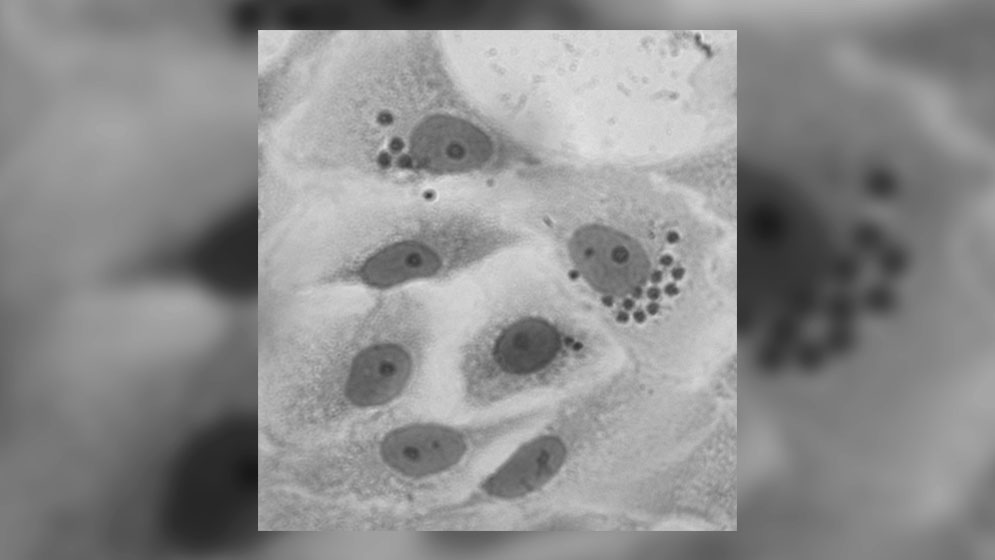

Un estudio de especialistas del CONICET muestra que proteínas de la familia de los bromodominios están involucradas en la regulación de la expresión génica en Trypanosoma cruzi, el parásito causante de la enfermedad.scopía electrónica. Células infectadas con Trypanosoma cruzi.

El artículo recientemente publicado es la primera parte de la caracterización de la proteína Factor de Bromodominio 2 de Trypanosoma cruzi (TcBDF2). “Pudimos ver que BDF2 se expresa durante todo el ciclo de vida del parásito y resulta esencial para su crecimiento y proliferación, tanto en el insecto vector como dentro de las células humanas”, indica Serra. Una vez establecida la importancia de esta proteína comenzó la búsqueda de compuestos que interactuaran con BDF2 inhibiendo su función. Explica Victoria Alonso: “Pusimos a punto un ensayo in vitro y vimos que había una interacción con varios inhibidores comerciales de bromodominios. Seleccionamos uno de ellos para usarlo como sonda y buscar en más de 22 mil compuestos provistos por Glaxo, cuáles podrían tener más afinidad para unirse a BDF2”. Como resultado de este estudio, realizado en una plataforma abierta de la empresa en España, se seleccionaron diez compuestos que actúan como inhibidores de BDF2, algunos de ellos “tienen estructuras químicas muy originales”, asegura Serra y adelanta que una vez que arriben al país los compuestos seleccionados, realizarán experimentos en su laboratorio para analizar el efecto que tienen sobre T. cruzi. Según Alonso, estos análisis pueden ser el punto de partida para modificar los compuestos identificados y aumentar su eficacia como drogas para controlar la infección por el parásito.